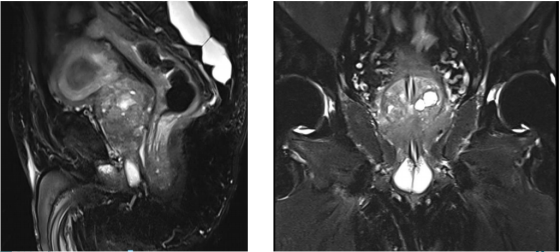

MRI:中央带、移行带、外周带异常信号,突破包膜、累及尿道;PI-RADS评分5分。

图1 2024年11月23日MRI检查